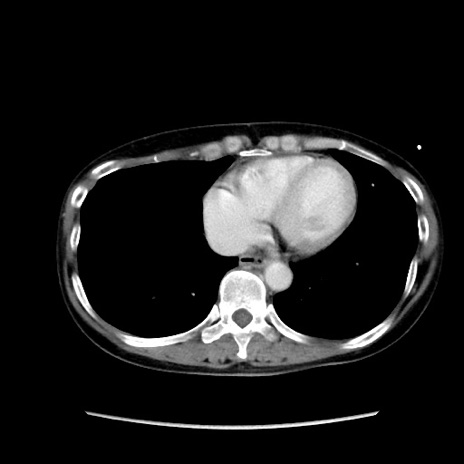

症例32(横断像)

【症例】40歳代 女性

【主訴】上腹部痛、嘔気・嘔吐

【現病歴】約9時間前頃から急に上腹部痛、嘔気、嘔吐が出現。改善しないため救急要請。

【既往歴】子宮頚癌(広汎子宮全摘術、放射線療法)、腸閉塞

【身体所見】腹部:平坦、軟、腸雑音亢進、上腹部を中心に腹部全体に圧痛あり。

【データ】WBC 8400、CRP 0.03